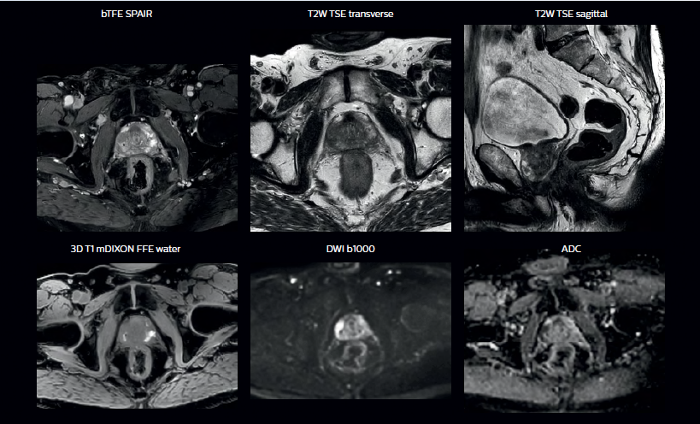

With its exceptional soft-tissue visualization capabilities and wide range of image contrasts, MRI has become a powerful tool to help more precisely define tumor boundaries. This is particularly important as it has been established that there is a high degree of uncertainty in target volume delineation, and it is even reported to represent the largest uncertainty in the entire radiotherapy process for most tumor sites**. Better visualization of the target area and nearby organs-at-risk is a key factor in enhancing target volume delineation. MRI’s expanding role also can be attributed to its functional imaging capabilities, which can inform both target characterization and treatment response.

Ingenia MR-RT is a dedicated MR simulation platform that provides high quality, high contrast MR images acquired with the patient in treatment position. Designed for the needs of radiation oncology, this comprehensive solution provides the tools and software needed for versatile and efficient imaging for radiotherapy planning.

Our innovative MRCAT (MR for Calculating ATtenuation) clinical applications lets you plan radiation therapy using MRI as primary imaging modality. Within just one, fast MR exam, MRCAT provides both excellent soft-tissue contrast for target and OAR delineation and CT-like density information for dose calculations.